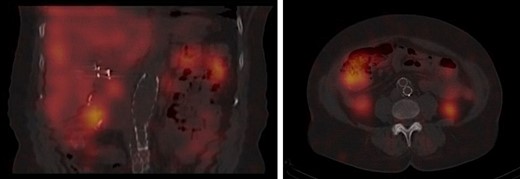

Given her history of an ileal carcinoid tumor, we next ordered an Octreotide scan, which showed no focal abnormality in the abdomen (Fig. 4). After discussing potential treatment options, following preoperative evaluation the patient underwent a left breast lumpectomy with wire localization. She tolerated the procedure well and is currently being managed through active surveillance.

Octreotide scan showing normal accumulation in the liver, spleen, kidneys and bladder with no focal abnormality in the abdomen.